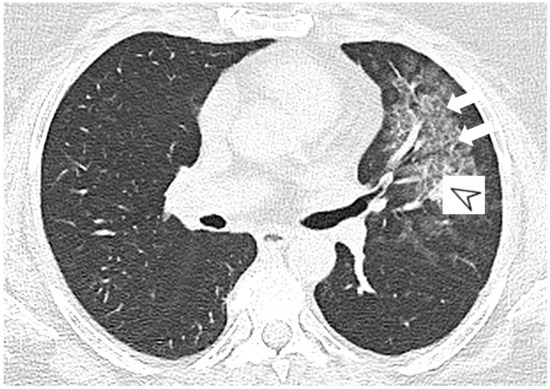

2.4. Granulomatosis with Polyangiitis (GPA-Wegener’s Disease)

| GPA | Solid nodules, GGOs due to hemorrhagic alveolitis (common); halo sign, crazy paving (less common) |